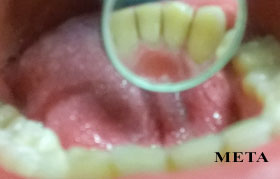

λεύκανση